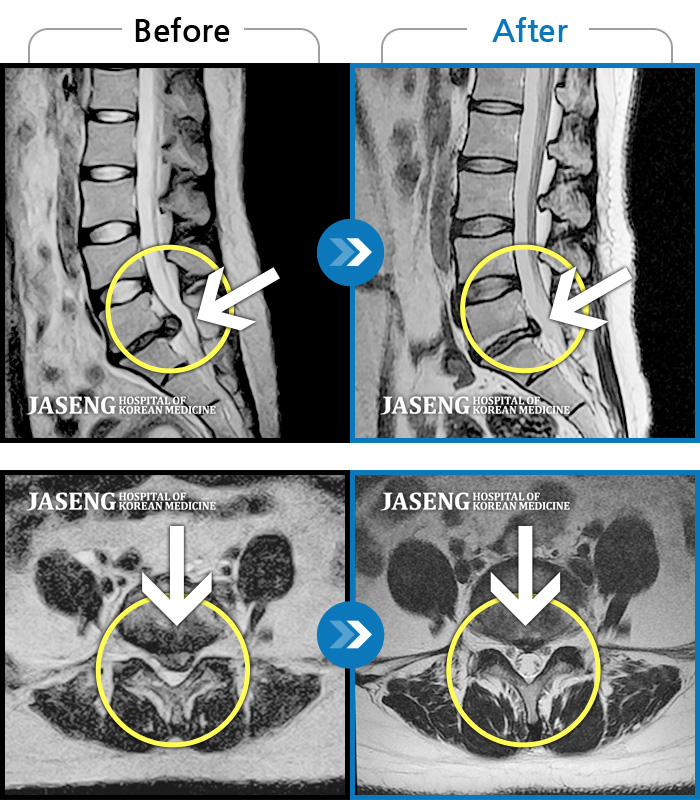

MRI 치료사례

좌측다리로 저리고 통증, 허리 숙일 때 다리 당김